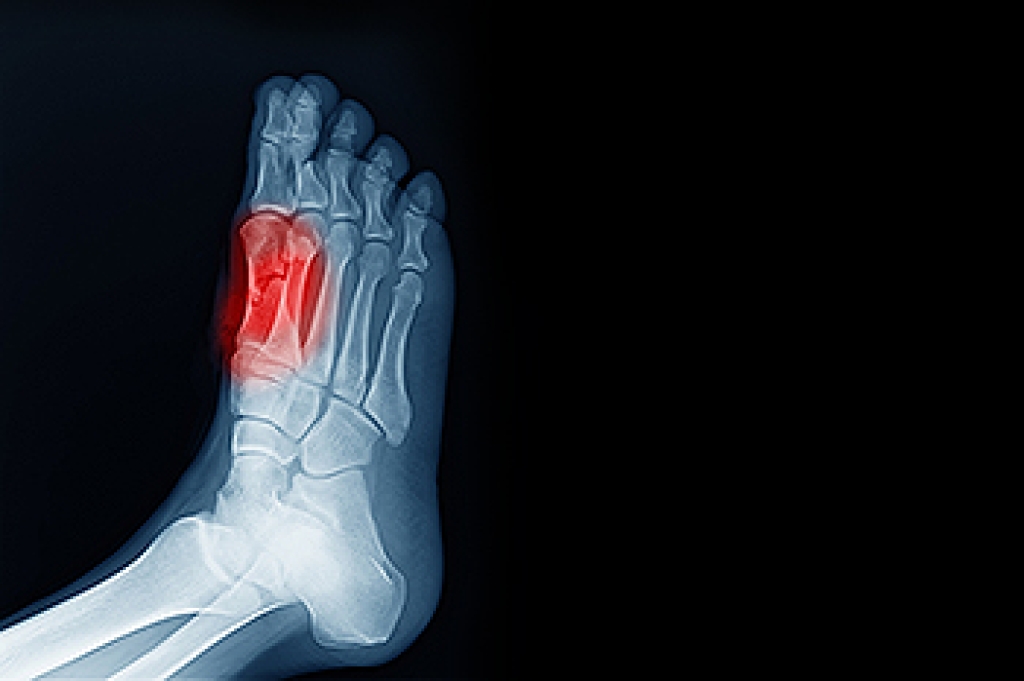

Sesamoiditis is a painful condition involving two small bones located beneath the big toe joint. These sesamoid bones are embedded within a tendon that helps flex the big toe and absorb weight-bearing pressure. When repetitive stress or trauma affects this area, the surrounding tendon can become inflamed, causing pain beneath the ball of the foot. High-impact sports, foot injuries, poor foot mechanics, or shoes that lack adequate support can increase the risk of sesamoiditis. Symptoms include swelling, tenderness, and sharp pain when bearing weight or bending the big toe. This often builds gradually and may make walking or running difficult. A podiatrist can diagnose sesamoiditis by examining the foot, checking for tenderness, and ordering imaging tests to rule out fractures or other problems. In severe cases, surgery may be recommended to remove or repair the affected bone. If you have this type of pain in the big toe, it is suggested that you schedule an appointment with a podiatrist for an exam and appropriate treatment options.

Sesamoiditis is a condition of the foot that affects the ball of the foot. It is more common in younger people than it is in older people. It can also occur with people who have begun a new exercise program, since their bodies are adjusting to the new physical regimen. Pain may also be caused by the inflammation of tendons surrounding the bones. It is important to seek treatment in its early stages because if you ignore the pain, this condition can lead to more serious problems such as severe irritation and bone fractures.